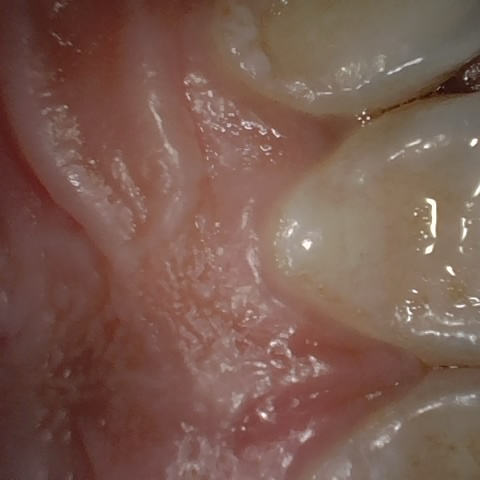

NHD20634

Annotated as "Good"